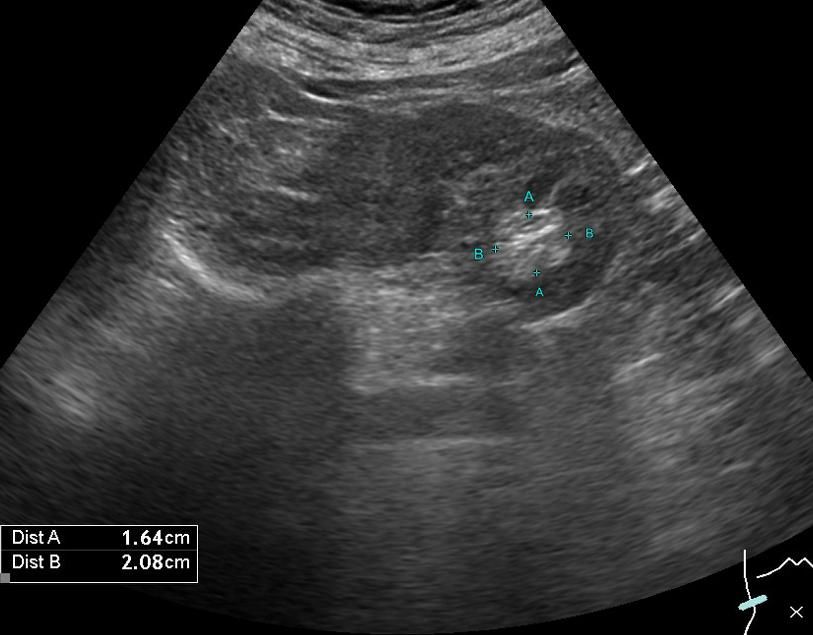

251231 건강검진으로 복부초음파 했는데 "우측 신장 2.08cmx1.64cm크기의 고에코 결절"로 복부 CT 해보라고해서

• 1번 째 사진

초음파에서 보인 고에코 결절은 실제 종양이 아니라 지방조직, 혈관 반사, 신우 구조, 석회화 미세반사, 장가스 영향 등으로 생기는 위양성인 경우가 적지 않습니다. 특히 신장은 초음파에서 검사자 숙련도, 호흡, 체형, 각도에 따라 같은 부위가 다르게 보일 수 있습니다. 같은 기관에서 반복 초음파를 했는데 크기 변화 없이 비슷하게 보였다는 점도 실제로는 구조물 또는 양성 변화일 가능성을 높입니다.

반면 CT는 신장 병변 평가에서 공간 해상도와 재현성이 높아, 2cm 전후의 고형 종괴나 의미 있는 낭종은 대부분 확인됩니다. CT에서 양측 신장, 요관, 방광 모두 특이 소견이 없었다면 임상적으로 의미 있는 신장 종괴 가능성은 매우 낮다고 판단합니다. 과거 CT에서 언급된 tiny renal cyst 역시 변화 없이 사라지거나 의미 없는 단순 낭종으로 보입니다.

현재까지의 검사 흐름을 종합하면 초음파상의 고에코 결절은 실제 병변이 아닌 영상 차이로 보이며, 추가 침습적 검사가 필요한 상황은 아닙니다. 보수적으로 접근한다면 6개월에서 1년 후 추적 초음파 정도로 충분하고, 증상이 없으면 더 적극적인 조치는 보통 권하지 않습니다.